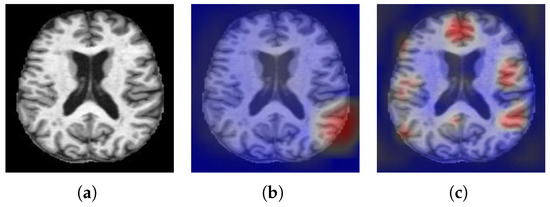

The AD dataset used in our work come from the OASIS (Open Access Series of Imaging Studies). The MR brain image samples of NC and AD in the dataset are shown in Figure 3. The dataset consisted of 416 subjects. We randomly selected 80 AD and 80 NC subjects, a total of 160 subjects. The grouping of AD and NC is determined by the Clinical Dementia Rating (CDR), 0 indicates NC, greater than 0 indicates AD. The scoring criteria is shown in Table 1. There are a lot of images for us to choose from in 3D MRI scanning, but selecting the best training data is still critical to the success of the method. Therefore, we calculate the image entropy of each slice and select the slice with a large amount of information as the training data. Image with probabilities p 1 , p 2 , , p M , the image entropy is calculated as shown in formula (4).

Figure 3. Samples of OASIS dataset. (a) AD. (b) NC.